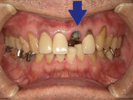

歯がこのままではダメだと思い、一念発起された50代女性の方です。

もちろん治療期間が長期にかかることも、治療費が高額になることも、外科的な手術が何度か必要であることなど、

インプラント治療と咬み合わせ治療のほぼ全てを大名歯科ホームページで予め知っていただいた上で決心され来院されたそうです。

インプラント治療は顎骨が乏しかったため、増骨手術も併用しなければならない難症例でした。

治療期間中は残存歯数が少ない上に、丈夫でないため生活に不自由な点がでました。

さらに咬み合わせが安定しにくい症例のため、プラスチック仮歯がよく壊れたり、外れたりして、修理に来院していただくなど大変な苦労とご迷惑をおかけしました。

審美性(見た目)は十分回復できたと思っており、患者さんも大変満足されています。

食事は当然のことかもしれませんが、よく咬めるようになったそうです。

咬み合わせ治療は非常に難しいため、これで十分かどうか分かりませんが現在もこのまま定期的なメインテナンス中です。